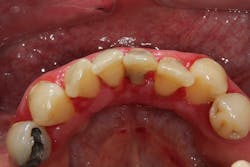

- 10% to 20% of the cases are typically attributed to calcium channel blockers, with nifedipine being the most notable problem (figures 4a and 4b).

Another laser that has been used to treat gingival enlargement and gummy smiles is a 9.3 micron CO2 laser (Solea from Convergent Dental; figure 2a). Unlike other lasers, the Solea laser has the capabilities of removing both soft and hard tissue, precise cutting accuracy due to control of both laser beam power and size, and the ability to cauterize inflamed tissue (figures 4c and 4d). Conventional instrumentation—such as blades, knives, and high-speed burs—can often lead to bleeding after surgical removal when the tissue is inflamed. With this type of CO2 laser, sutures and/or surgical dressing are often not needed.